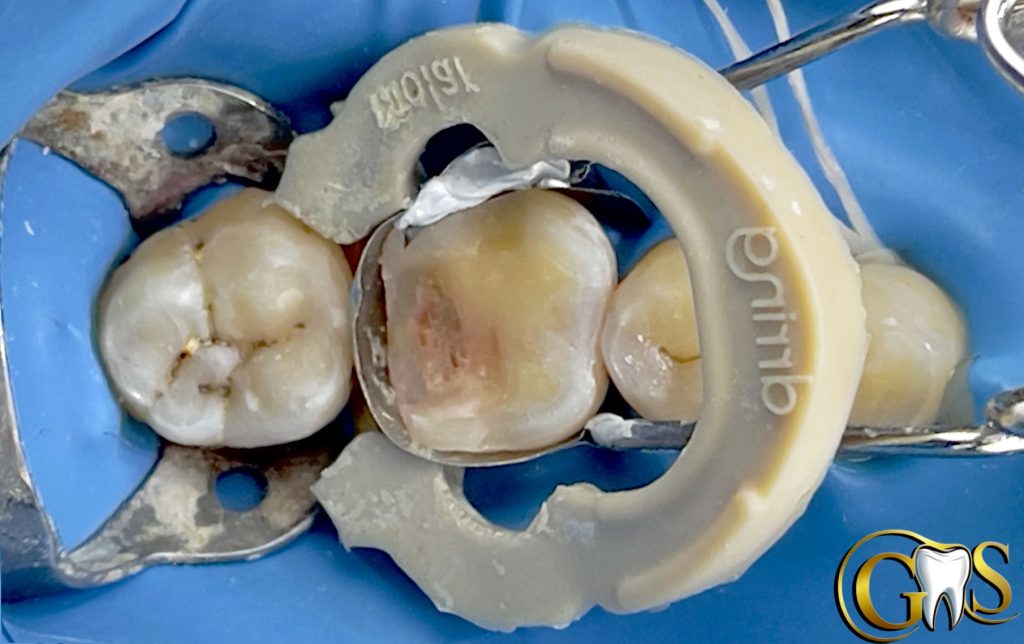

Saving vitality of LR6 (46) with Biomimetic Approach

A 34y female patient camed to our clinic complaining from food stagnation in lower right first molar with no signs of pain .. after diagnosis and sensibility test my decision was to save pulp vitality .

2-selective etching using charm etch (37%phosphoric Acid)

3-cotton Dampened in Chlorohexidine for MMps inhibition

4-IDS

5-Resin coating